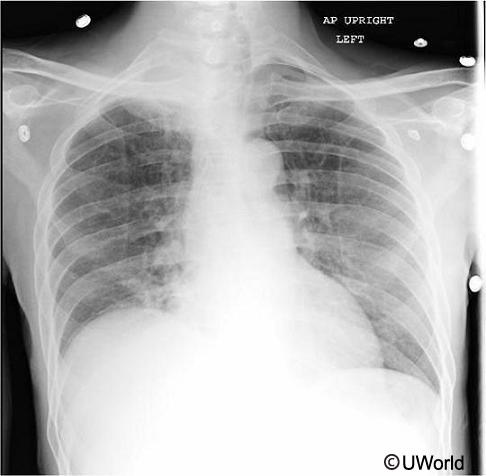

A 58-year-old man comes to the office due to progressive right-sided neck and arm pain. The pain started approximately 3 months ago, and the patient saw a chiropractor. Despite neck manipulation, he continues to have pain. Lately, the pain has become constant and is associated with numbness and tingling in his right forearm that extends to the tips of his fourth and fifth fingers. The patient’s symptoms are becoming more severe and awaken him at night. Acetaminophen no longer provides any relief. His chest x-ray is shown below.

This patient’s current symptoms are most closely related to which of the following?